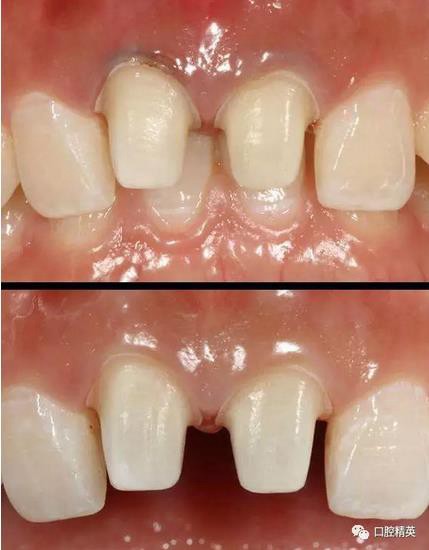

修復(fù)體戴入

口內(nèi)正側(cè)位及切端特寫

從側(cè)位照可看出遠(yuǎn)中切角略有回收

術(shù)前,術(shù)中,術(shù)后對(duì)比

對(duì)比來看基本達(dá)到患者預(yù)期

有一點(diǎn)不足之處在于齦緣的高低不完全一致,補(bǔ)救辦法同上——激光輕掃